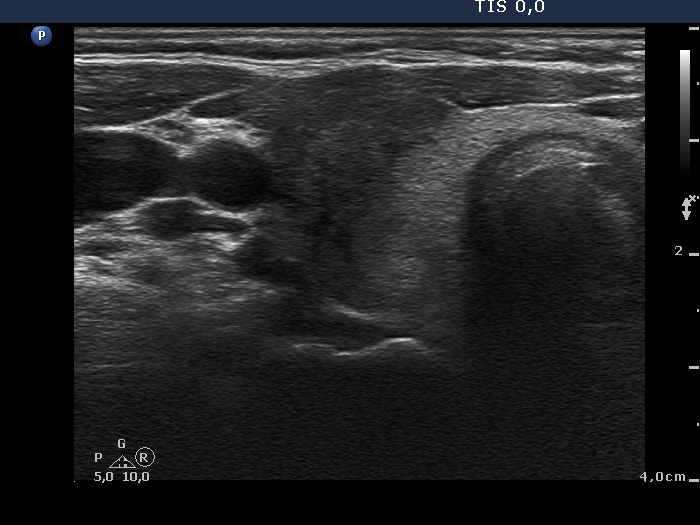

Initial examination (first row of images):

Clinical presentation: A 39-year-old woman was referred for evaluation of neck complaints lasting for more than a month. The patient had fever, neck pain. She has got two courses of antibiotics and non-steroid anti inflammatory drugs which had no effect.

Palpation: The right lobe was painful and hard while the left lobe was tender.

Laboratory examination: TSH 0.01 mIU/L, FT4 29.1 pM/L, FT3 7.45 pM/L, CRP 31.2 mg/L.

Ultrasonography: The thyroid presented with hypoechoic areas which had blurred borders. The echogenicity index was approximately 65% in the right and 20% in the left lobe. The thyroid was almost completely avascular.

Diagnosis: subacute, granulomatous de Quervain's thyroiditis.